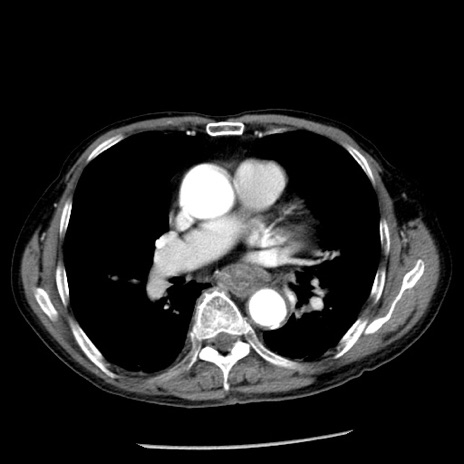

冠状断像

【症例】80歳代男性

【主訴】嘔吐

【現病歴】昨晩2回嘔吐あり、今朝になっても嘔吐あり。来院。

【既往歴】胃潰瘍

【身体所見】意識清明、BT 37.6℃、BP 166/95mmHg、HR 100bpm、SpO2 97%、腹部:平坦・軟、腸蠕動音聴取良好、圧痛なし。

【データ】WBC 21900、CRP 1.46